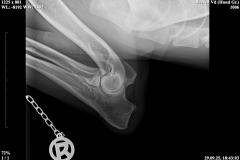

HD ZW: kW25/02 „69“ Größen-ZW: kW25/02 „101!